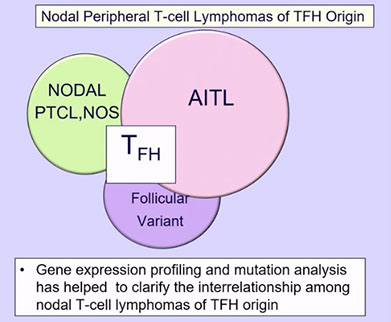

Angioimmunoblastic T-cell lymphoma and other nodal lymphomas of T follicular helper (TFH) cell origin

- Angioimmunoblastic T-cell lymphoma

- Follicular T-cell lymphoma

- Nodal peripheral T-cell lymphoma with TFH phenotype